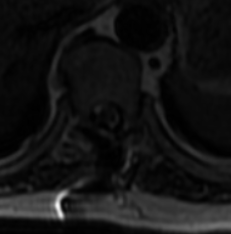

此处黄韧带骨化严重,脊髓压迫严重,椎管狭窄处约只有4mm。考虑到手术难度较大,传统麻醉下手术瘫痪风险甚至可达20%以上,2022年6月24日科室内部邀请医务部参与最终讨论,报请重大手术,并决定使用局部麻醉与全凭静脉麻醉联合,保持术中唤醒随时检查下肢运动功能的麻醉方式,利用椎间孔镜可以直视的优点,行椎间孔镜下胸椎后路T9-T10椎板切除减压、黄韧带摘除、脊神经探查松解术。在2022年6月25日经过长达4小时20分钟的精细操作下最终将患者的压迫解除。几乎完整取出了巨大的骨化黄韧带。

术后积极控制血糖、血压,预防并发症,术后复查见: